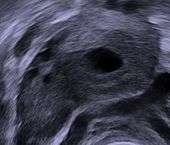

Human ovary with fully developed corpus luteum